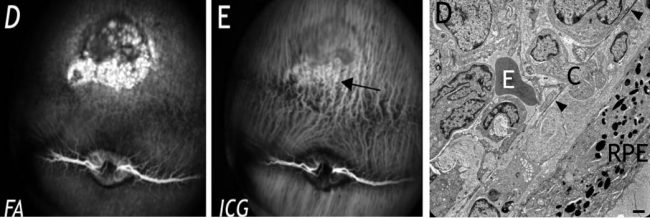

- Retinal Pigment Epithelium (RPE) toxicity assessment

- Retinal Pigment Epithelium (RPE) toxicity assessment